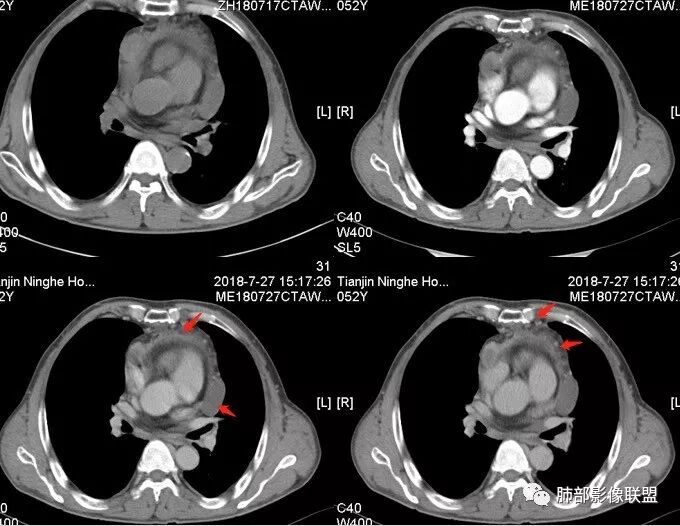

大雄:中年男性,发现左前胸壁血管曲张1天入院肿标:细胞角蛋白19片段明显增高,神经元特异性烯醇化酶稍高CT:前纵膈巨大实性占位,边缘膨隆,质地较硬,纵膈脂肪间隙模糊,压迫纵膈大血管(头臂静脉明显狭窄)但未见包绕。平扫可见囊变及钙化,增强中度延迟强化,可见大片不规则坏死区。未见纵隔淋巴结肿大,胸骨骨质破坏及胸水。考虑:恶性肿瘤,胸腺癌可能。

水晶石头 (许建林):患者中年男性,因左前胸壁血管曲张1天就诊。查体左颈前胸壁、左上臂静脉曲张。血管彩超左颈内血静脉流淤滞。肿标:细胞角蛋白19片段明显增高,神经元特异性烯醇化酶稍高胸部CT:前纵隔巨大实性占位,边缘膨隆、清晰,纵隔脂肪间隙模糊,压迫纵隔大血管,未见包绕。平扫可见囊变及钙化,增强中度延迟强化,可见大片不规则坏死区。未见纵隔淋巴结肿大、胸骨骨质破坏及胸水。综合考虑恶性肿瘤,胸腺癌可能性大,鉴别恶性畸胎瘤。

崔少钢:中年男性,左侧颈内静脉、左侧前胸壁及左上臂静脉曲张,提示有静脉阻塞,另患者有恶性家族史。影像:前纵隔占位,有浅分叶,周围脂肪间隙不清晰,且见小淋巴结,内有坏死,上腔静脉受侵,内有钙化,支持胸腺癌。

南边:边界大部分清楚,有些地方毛糙。

上腔静脉如何?

心包如何?

大肿块,边缘不清,伴随肿大淋巴结,上腔静脉受侵犯——恶性